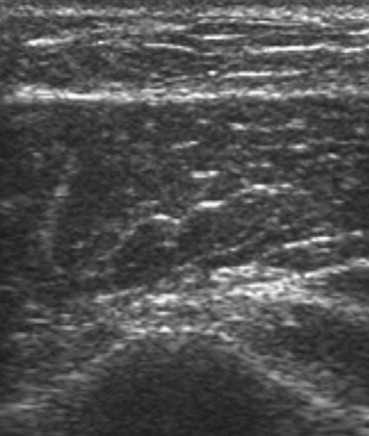

Fig. 5.

Isoechoic subcutaneous nodular lesion visualized at conventional imaging (BMCI).

Fig. 6.

Same scan as Fig. 5 after activation of harmonic imaging (THI).